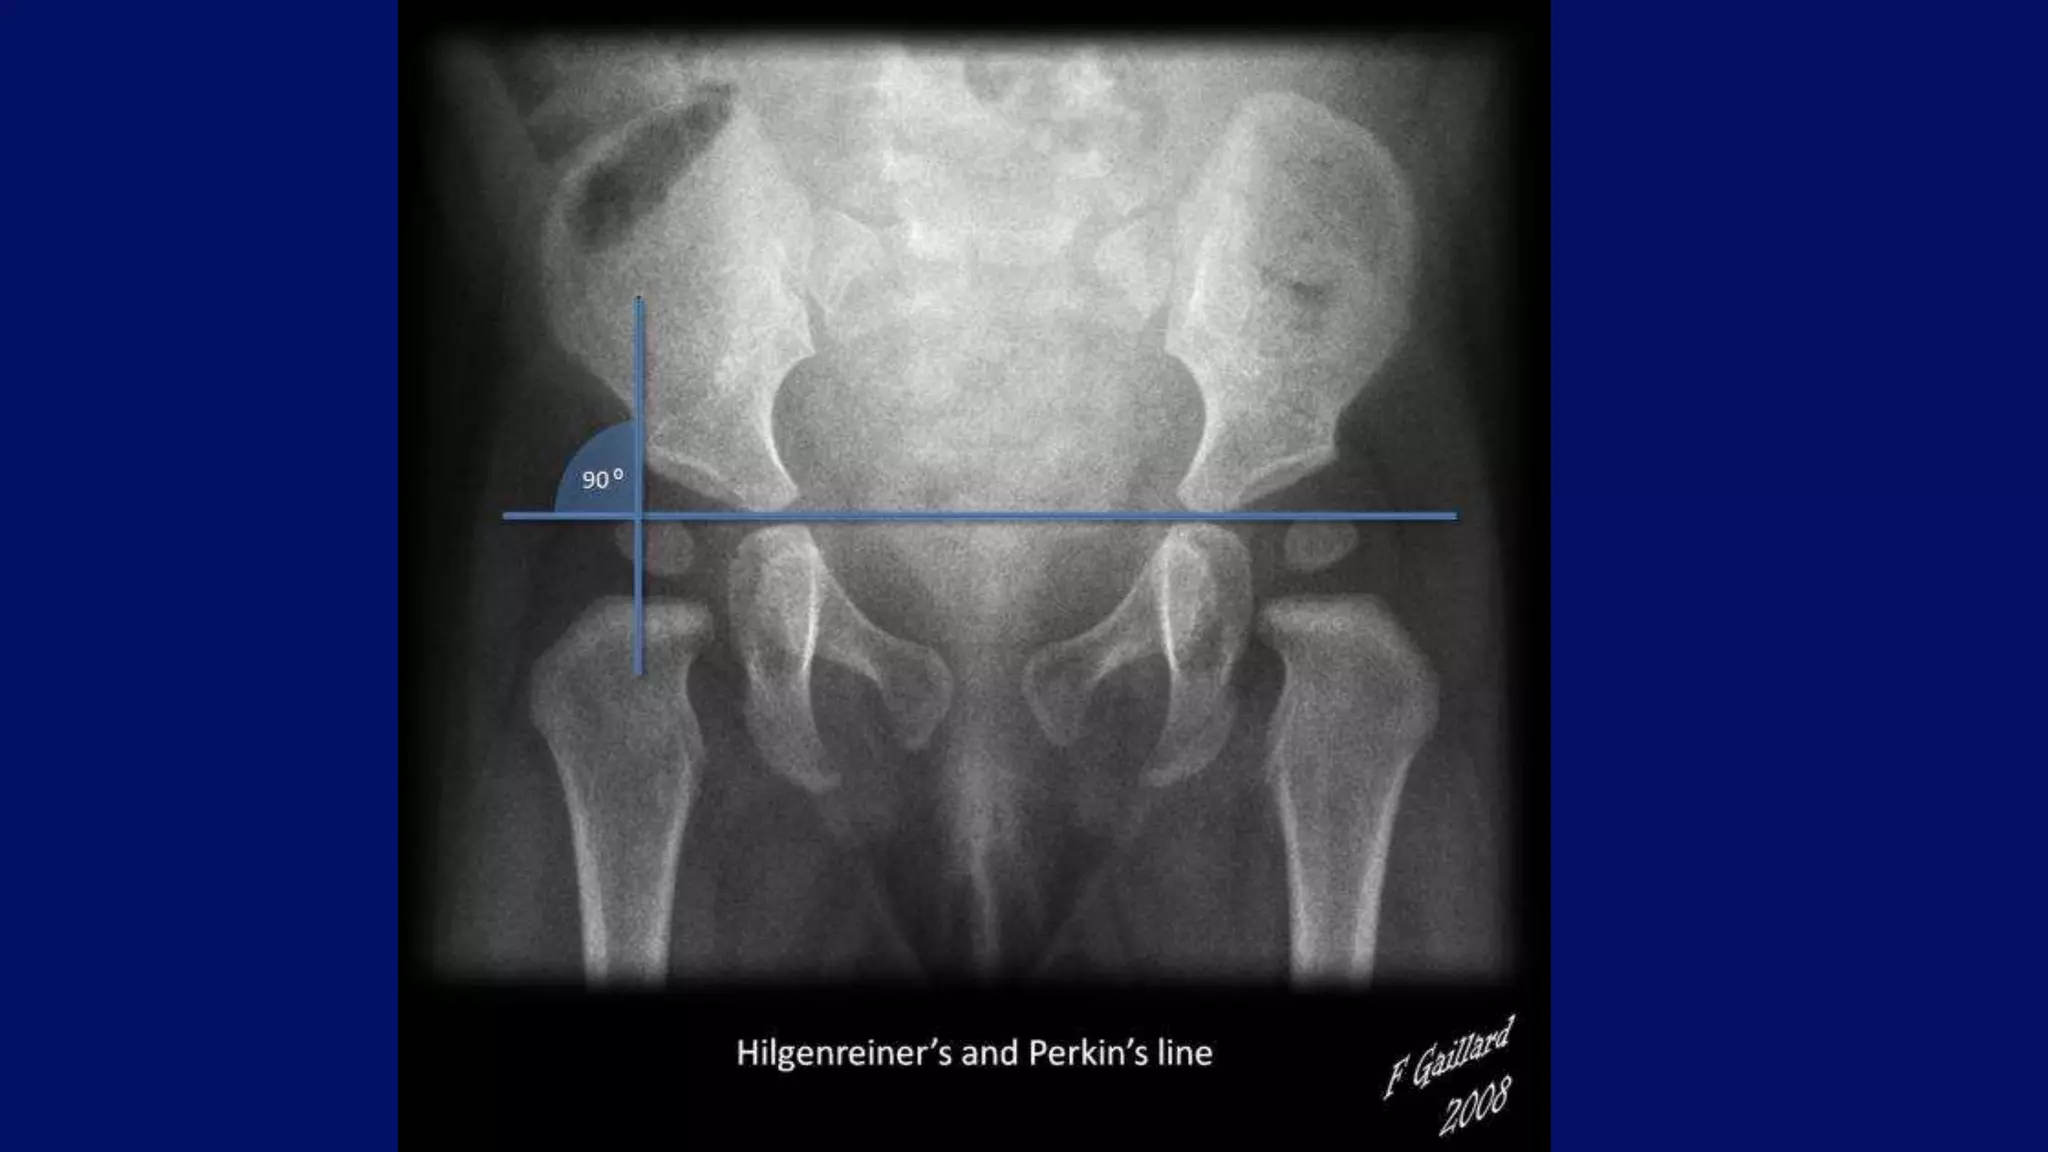

•Putti's triad for developmental dysplasia of the

hip include :

Superolateral displacement of proximal femur .

Increase in acetabular angle.

Small capital femoral epiphysis.

Developmental dysplasia of the hip

Radiograph demonstrates Developmental Dysplasia of Hip in a 6 months old female baby.

• #65 The center-edge (C-E) angle of Wiberg is helpful in evaluating the development of the acetabulum and its relation to the femoral head. A baseline is projected, connecting the centers of the femoral heads. The C-E angle is formed by two lines originating in the center of the femoral head, one drawn perpendicular to the baseline into the acetabulum, and the other connecting the center of the femoral head with the superior acetabular lip. Values below the lowest normal value given for each age group indicate hip dysplasia.

• #68 36 degree acetabular angle.